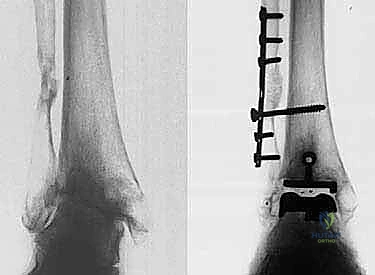

- الأشعة السينية (X-rays) بوضعية الوقوف: وهي الأداة الذهبية للتشخيص. صور الأشعة والوزن محمل على القدم (Weight-bearing X-rays) تظهر بدقة مدى تآكل الغضروف (ضيق المسافة المفصلية)، وجود نتوءات عظمية (Osteophytes)، وأي انحراف في المحور الميكانيكي للساق.

* التثبيت: هو مفصل "غير إسمنتي". يتم تغطية الأسطح المعدنية الملامسة للعظم بطبقة مسامية من التيتانيوم وهيدروكسي أباتيت (Hydroxyapatite). هذه الطبقة تشجع العظم الطبيعي للمريض على النمو داخل مسام المفصل (Bone Ingrowth)، مما يوفر تثبيتاً بيولوجياً صلباً يدوم لسنوات طويلة.

* التصميم الميكانيكي: يشارك هذا النظام نفس الهندسة التشريحية الممتازة للمكونات المعدنية لنظام سالتو، ولكن مع اختلاف جوهري واحد: المكون البلاستيكي (البولي إيثيلين) هنا ثابت (Fixed-bearing) ويتم قفله بإحكام داخل المكون المعدني العلوي (الظنبوبي).

* الفلسفة وراء التصميم: أثبتت الأبحاث وخبرة الجراحين، بما في ذلك الأستاذ الدكتور محمد هطيف، أنه إذا تم إجراء القصات العظمية أثناء الجراحة بدقة متناهية تتوافق مع التشريح الطبيعي، فإن الحاجة إلى حركة واسعة للمكون البلاستيكي تقل بشكل كبير.